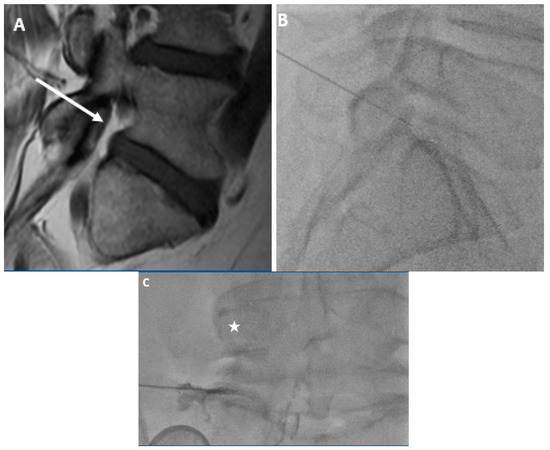

In this study, we demonstrated a difference in the distribution of foraminal fat in the postero-inferior and antero-superior foramen. In this population, 80% of L5-S1 foramina with moderate to severe stenosis had at least minimal postero-inferior epidural fat while just 40% of these same foramina had at least minimal fat in the antero-superior neural foramen. In fact, none of the foramina with moderate to severe stenosis had more than minimal foraminal fat in the antero-superior foramen. Even in patients without stenosis, more than 10% had no fat (“None”) in the antero-superior foramen, and only 31.6% had more than minimal fat in this location. Postero-inferiorly, all patients without foraminal stenosis had substantial foraminal fat. These findings for the L5-S1 foramen may support the notion that the postero-inferior approach (“Kambin’s triangle) for L5-S1 TFESI may be more advantageous than one in which the antero-superior foramen (“Safe triangle”) is targeted (Figure 3).

Figure 3.

59-year-old gentleman with L5 radiculopathy. (A) Sagittal T1w MR image demonstrates substantial fat in the postero-inferior foramen. The arrow corresponds to the needle trajectory for an infra-neural approach. Lateral (B) and frontal (C) fluoroscopic images during transforaminal epidural steroid injection show the needle projecting over the postero-inferior aspect of the foramen. The star is over the pedicle in (C). Contrast can be seen moving centrally towards the spinal canal within the inferior portion of the foramen.